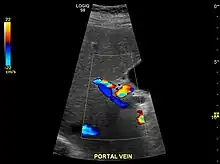

Ultrasound is routinely used in the evaluation of cirrhosis.[34] It may show a small and shrunken liver in advanced disease. On ultrasound, there is increased echogenicity with irregular appearing areas.[51] Other suggestive findings are an enlarged caudate lobe, widening of the fissures and enlargement of the spleen.[52] An enlarged spleen, which normally measures less than 11–12 cm (4.3–4.7 in) in adults, may suggest underlying portal hypertension.[53] Ultrasound may also screen for hepatocellular carcinoma and portal hypertension.[34] This is done by assessing flow in the hepatic vein.[54] An increased portal vein pulsatility may be seen. However, this may be a sign of elevated right atrial pressure.[55] Portal vein pulsatility are usually measured by a pulsatility indices (PI).[54] A number above a certain values indicates cirrhosis (see table below).